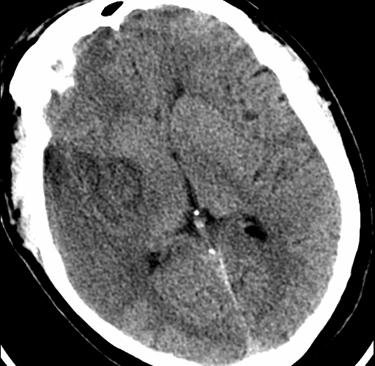

Accident ischémique cérébral sylvien droit superficiel

Hypodensité précoce traduisant un accident ischémique cérébral (AIC) sylvien droit superficiel.